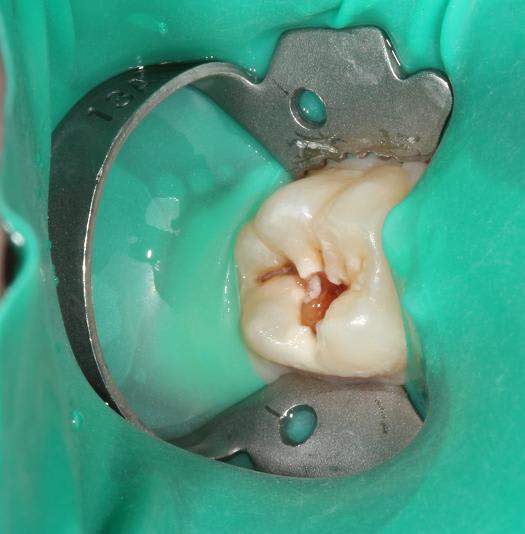

Quelques photos pour illustrer le sujet initial. Dommage que ces dents n'aient jamais eu de sealants.

Pour l'effraction pulpaire sur dent asymptomatique, je fais le protocole que Choixpeau avait mis sur le forum : hypochlorite puis adhésif directement au contact. Aucun problème à court terme pour le moment.

Si effraction plus importante : MTA.